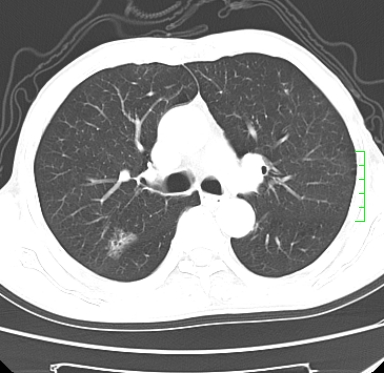

m,73y。膝关节疼痛伴双下肢水肿。入院常规胸片发现结节灶。增强为静脉期。

浅分叶、棘突,考虑右下肺周围型肺癌

肿块周围可见局限性气肿,考虑肺癌可能性大。双肺上叶继发型肺结核。

指套征,强化明显,近侧肺组织局限性肺气肿,考虑支气管类癌,慢支、肺气肿、双上陈旧性tb、冠脉钙化。

鉴别:先天性支气管闭锁,变态反应性支气管肺曲霉菌病,肺癌,支气管囊肿,支扩黏液嵌塞。

1)考虑右肺下叶周围型肺癌。2)右肺上叶及左肺感染性病变(结核可能)。3)肺气肿。4)冠状动脉钙化。